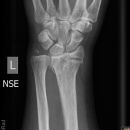

Lunatummalazie